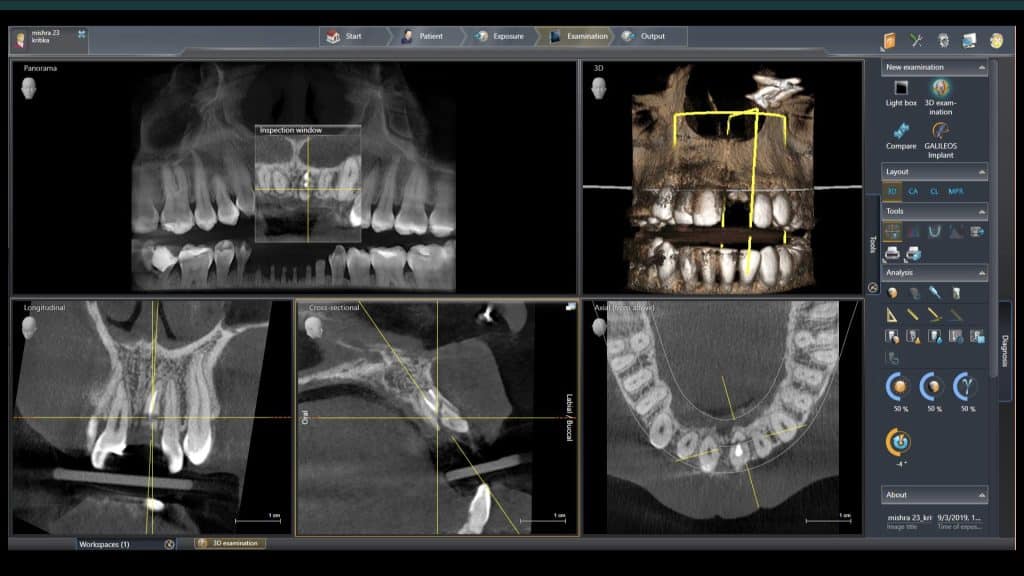

A 27-year female patient with dislodged Resin bonded FPD. She had that FPD for past few years, it had metal wings on palatal surfaces of UR1 and UL2 and a post like metal extension into the root canal of UL1. There was gingival abscess due to fractured root segment most probably due to extended metallic post like structure. Immediate implant placement (IIP) and Immediate restoration (IR) was planned for this patient.